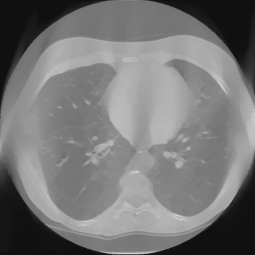

Refer to caption

Figure 9: The inpainted sinogram and reconstructed images for test datasets of lung CT from Data Science Bowl 2017. We compair three reconstrucion methods: FBP, our proposed supervised-trained network, and iterative SART reconstrucion with TV regularization. Both the proposed network and SART-TV method reduce the streaking artifacts. And our results have less cartoon-like artifacts than SART-TV. The display window is [-1, 1].

Fig 9 and Table I demonstrate the experiment results for the lung CT data. Both the proposed network and SART-TV method reduce the streaking artifacts caused by the sinogram inconsistencies in angle, while SART-TV introduced piecewise constant cartoon-like artifacts because of the TV normalization. The quantitative studies indicate the superiority of the proposed method in terms of absolute error and structural.

TABLE I: Quantitative Comparsion for FBP, SART-TV and Proposed Method for Lung CT test dataset (113 images)

FBP SART-TV Proposed

avg. PSNR(dB) 22.51 25.23 33.86

avg. SSIM 0.9249 0.9088 0.9781